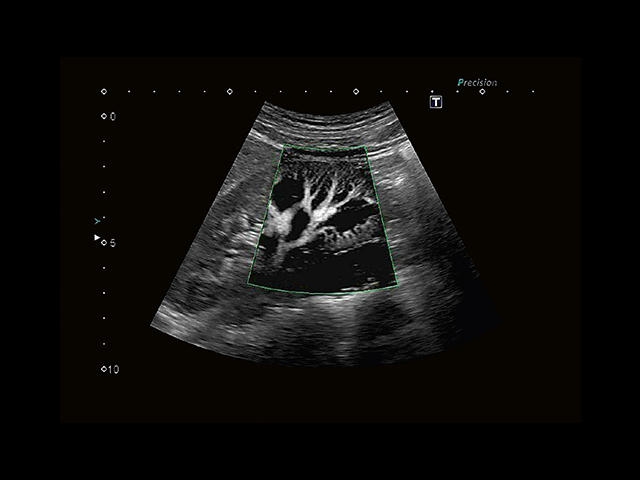

Aplio 500 – ультразвуковой сканер премиум класса, сочетающий в себе быстродействие диагностики и отличное качество визуализации. Более 30 датчиков на выбор, в т.ч. матричные, монокристаллические, 4D, эндоскопические для любых типов исследований. Ультразвуковой сканер позволяет изучать анатомические структуры в высоком разрешении.

Обновленная версия легендарного УЗ-сканера. Стационарный аппарат экспертного класса Aplio 500 Toshiba NEW, визуализирует анатомические структуры в высоком разрешении. Модель позволяет выявить микрокальцификаты, новообразования, нарушения в работе сердца, сосудов и мышц. Присутствует функция виртуальной эндоскопии, 4D-сканирования, эластометрии тканей, УЗИ с контрастированием. За повышение качества изображения отвечают технологии ApliPure и Superb Microvascular Imaging. Первая задействует возможности пространственного и частотного кодирования, формирует цельный визуальный ряд с сохранением клинических маркеров. Вторая улучшает отображение микрососудистого русла, используя доплеровский эффект. Модель оснащена 21-дюймовым монитором, имеет 4 активных порта. Возможно подключение педиатрических, интраоперационных, лапароскопических и чреспищеводных датчиков.

• Fly Thru. Виртуальная эндосонография обеспечивает построение трехмерной модели полостей, протоков и сосудов в рельном времени, облегчает организацию инвазивных процедур и динамических исследований. Посредством Fly Thru можно установить шунты и стенты, проводить точные оперативные вмешательства.